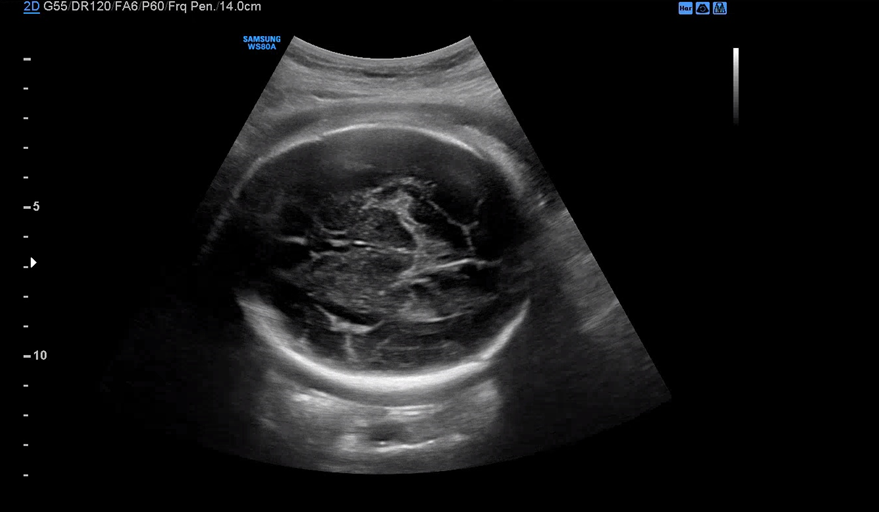

막달 검사를 마치고 30분 정도 대기한 뒤 원장을 진료를 봤다. 4분가량 배 초음파로 아기의 상태를 체크해주시는데 BPD, Fetal HR, AC, FL 순서로 봐주시고 마지막으로 아기 얼굴을 보여주셨다.

항상 이 시간에 자고 있는 우리 아기. 이번엔 초콜릿 우유를 먹지 않아서 그런지 얌전히 자고 있었다.

이제 점점 자궁이 좁아 불편할 텐데 그래도 얌전히 잘 버텨주고 있어 대견하다. 태동은 매일 느끼지만 내 기준 엄청 아프지 않은 것 같다.